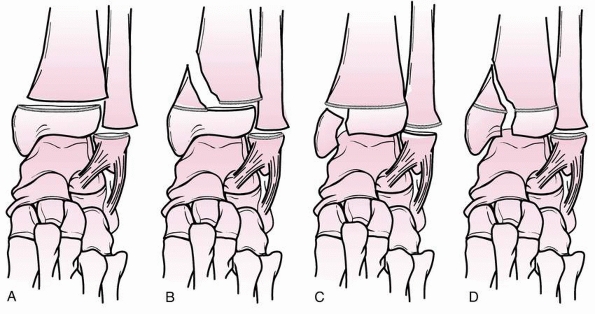

![]() |

FIGURE 26-3 Dias-Tachdjian classification of physeal injuries of the distal tibia and fibula.

|

FIGURE 26-4 Variants of grade II supination-inversion injuries (Dias-Tachdjian classification). A. Salter-Harris type I fracture of the distal tibia and fibula. B. Salter-Harris type I fracture of the fibula, Salter-Harris type II tibial fracture. C. Salter-Harris type I fibular fracture, Salter-Harris type III tibial fracture. D. Salter-Harris type I fibular fracture, Salter-Harris type IV tibial fracture.